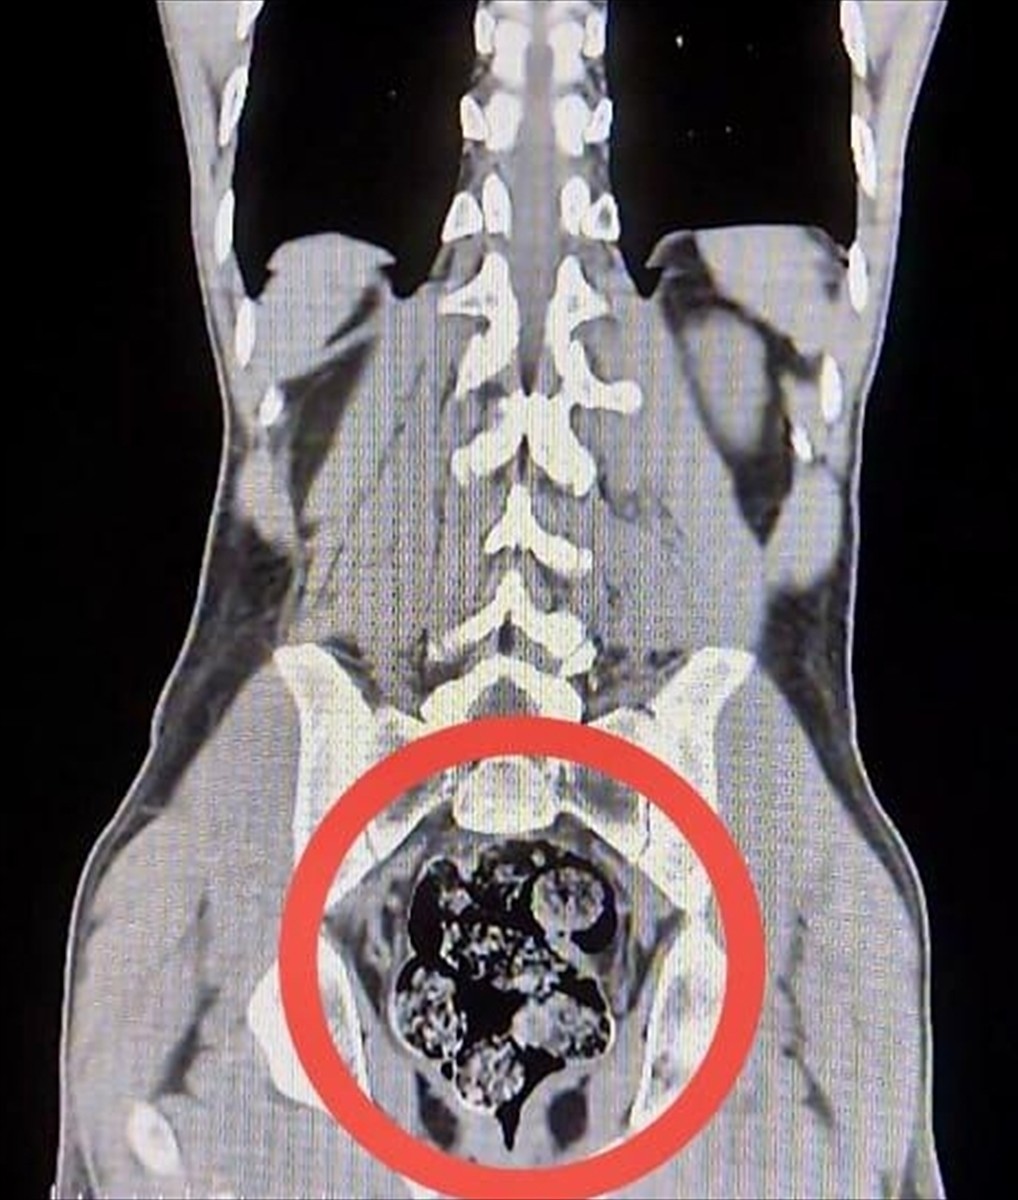

Gözaltına alınan zanlılar, Harakani Devlet Hastanesi'ne götürüldü. Yapılan incelemede, Amır Rafıeı S.'nin mide ve bağırsaklarında 7 parça halinde 203,02 gram sentetik uyuşturucu tespit edildi. Uyuşturucu madde cerrahi bir müdahale ile çıkarıldı.